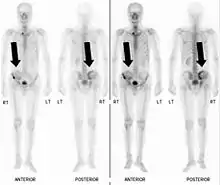

Fracture pathologique du bras gauche sur une métastase osseuse de cancer du sein Scintigraphie corps entier avec 99mTc-HDP de la patiente avec une fracture du bras due à une métastase du cancer du sein

Scintigraphie corps entier avec 99mTc-HDP de la patiente avec une fracture du bras due à une métastase du cancer du sein